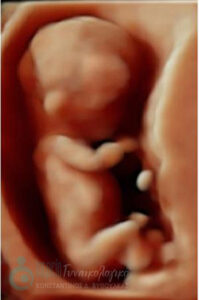

- Υπερηχογραφική εξέταση, η οποία συμβάλλει στη διαπίστωση της ενδομήτριας κύησης και αποκλεισμό της έκτοπης κύησης. Επιπλέον, μπορεί να διαπιστώσει εάν πρόκειται για μονήρη ή πολύδυμη κύηση, να ανιχνεύσει την εμβρυϊκή καρδιακή λειτουργία μετά τις 6 εβδομάδες και να προσδιορίσει υπερηχογραφικά την ηλικία κύησης, με βάση το κεφαλουραίο μήκος του εμβρύου μετά τις 8 εβδομάδες.